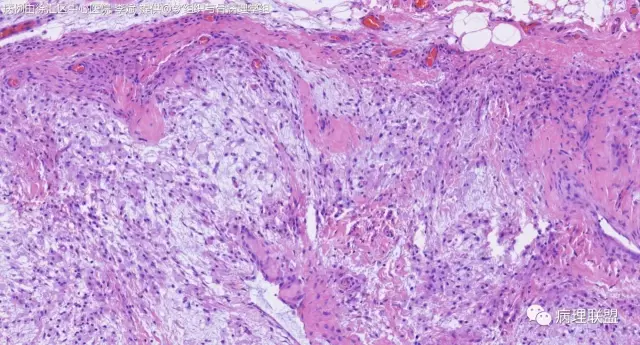

女,64岁,右腕部肿块,灰白不整形1*1*0.8cm(病例由徐汇区中心医院 李斌提供,致谢!)

神经鞘粘液瘤。

富于细胞神经鞘粘液瘤,s100阴。

关节旁粘液瘤,肿瘤中间明显有腱鞘囊肿结构,又发生在关节处!强烈提示为关节旁粘液瘤,部分病例可以呈分叶结构!平时多加观察腱鞘囊肿囊壁常可见粘液变性!范围一广就成粘液瘤样。

@周泉 周老师您好,李斌老师第一个病例里细胞都是上皮样的包浆宽的,嗜酸,粘液瘤细胞细胞梭的星形的,所以我考虑是神经鞘的了,您觉得粘液瘤细胞也可以这种形态吗?

@左淑英 部分应该是组织细胞